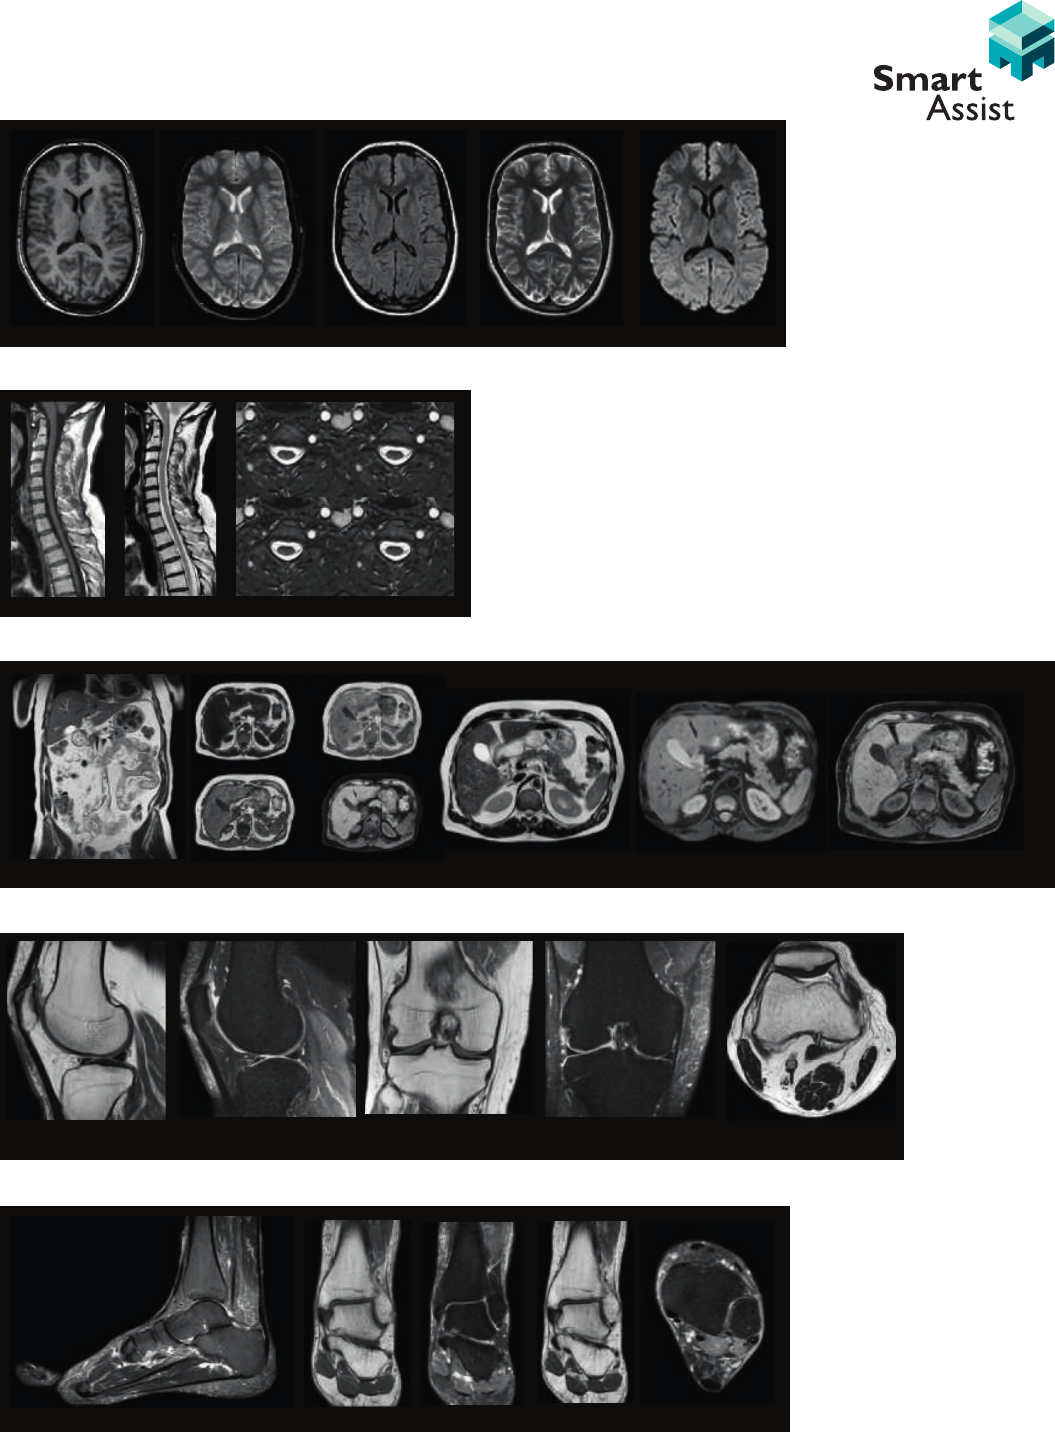

T1W FLAIRT2* T2 DWI

PDW SPAIR PDW SPAIR PDW SPAIR PDW SPAIRT1W

<8 minute Brain Exam

<8 minute Cervical Spine Exam

<8 minute Abdominal Exam

<8 minute Knee Exam

T1W T2W BFFE

T2W mDixon T2W DWI Dynamic mDixon water-only

<8 minute Ankle Exam

PDW T1WPDW SPAIR PDW SPAIR T2W

STIR T1W STIR PDW STIR

PDW

Imaging excellence for your

most common applications

The Ingenia 1.5T system’s dStream architecture and dS coil

solutions result in high SNR that benefits every application.

You no longer have to trade resolution for speed: now you

can perform routine exams for brain, spine, knee, ankle and

liver within less than 8 minutes with excellent image quality.